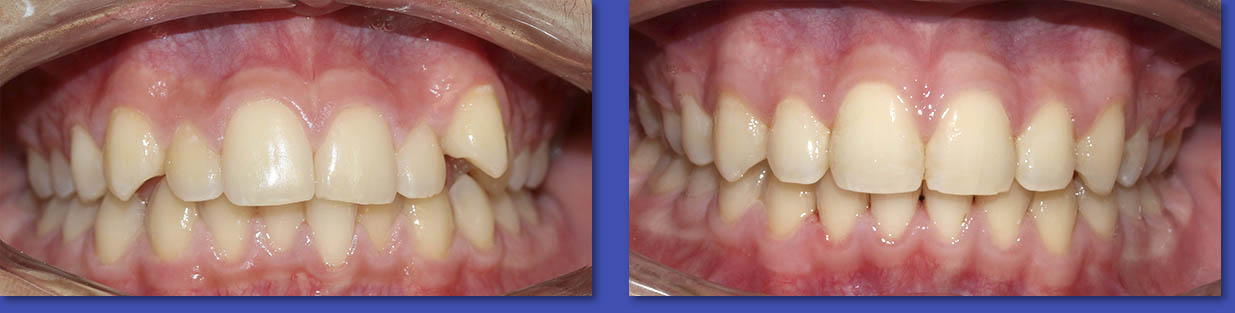

4. ORTODONCIA

La Ortodoncia se encarga del tratamiento de las anomalías de forma,posición,relación y función de las estructuras dentomaxilofaciales. La causa más común para el uso de aparatos de ortodoncia son las malposiciones dentarias o “ dientes chuecos “.

Ortodoncia

ANTES

DESPUÉS